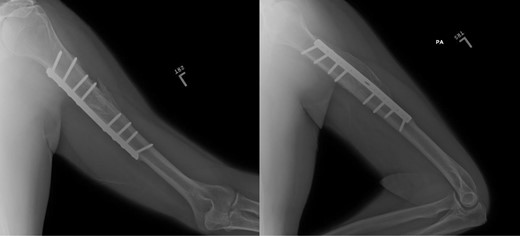

ML is a 52-year-old male who presents to our clinic complaining of severe left anterolateral arm pain after being involved in a motor vehicle accident 10 years prior to presentation. At that time, he had suffered a left mid-shaft humerus fracture treated with open reduction and internal fixation, as well as a traumatic brain injury and multiple other injuries to the right lower extremity resulting in the below-knee amputation. For the last several years he has had severe pain in the anterolateral aspect of the left arm, but denies any weakness or parasthesias. On physical examination, he demonstrates localized tenderness to palpation along the anterolateral aspect of the mid-humerus ~8–10 cm proximal to the lateral epicondyle. The patient had full motor function, though somewhat limited by pain, and sensation was intact to light touch throughout the radial nerve distribution. Plain films (Fig. 1) and CT-imaging (Fig. 2) show a healed fracture with acceptable alignment and hardware in good position. The patient elected to undergo lidocaine injection at the site of maximal tenderness, which gave excellent, albeit temporary pain relief, for about a week. Electrodiagnostic studies obtained at that time revealed chronic radial nerve neuropathy above the spiral groove.

Plain films, AP/lateral showing appropriate alignment of fracture.